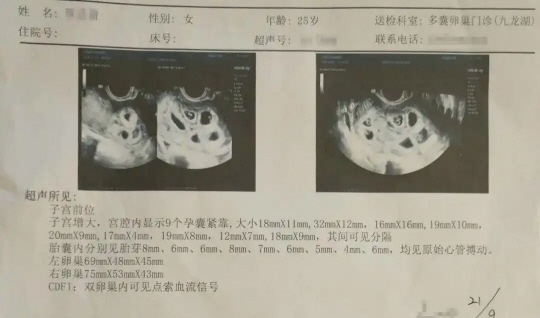

아홉 쌍둥이를 임신했던 여성의 초음파 사진. 사우스차이나모닝포스트(SCMP) 캡처

그는 결혼 후 1년간 아이가 생기지 않자 병원에서 배란 촉진제를 맞았고, 이후 임신을 확인하려 진행한 검사에서 무려 9개의 아기집을 발견했다.

아홉 쌍둥이를 임신했던 여성의 초음파 사진. 바이두 캡처